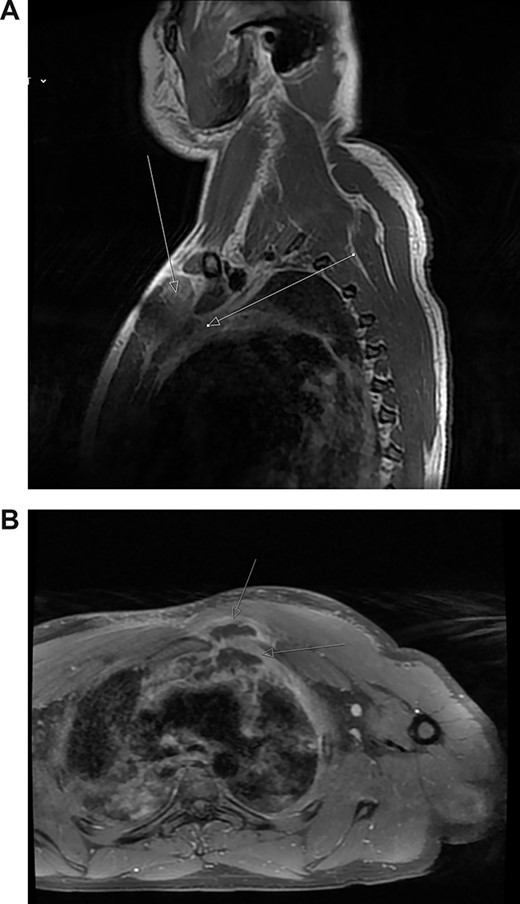

(A) Post-contrast MRI scan showing areas enhancement around pectoralis major (myositis) with extension into the mediastinum (mediastinitis) (white arrows). (B) New rim-enhancing collections within left pectoralis major muscle. The collection appears to extend posteriorly into the anterosuperior mediastinum (white arrows)

The patient was commenced on a regimen of intravenous flucloxacillin and clindamycin. Blood cultures subsequently grew methicillin-sensitive S. aureus. Despite antibiotics, his symptoms worsened. His neutrophils and CRP increased to 16 000 cells/μL and 404 mg/L, respectively. Repeat MRI scan on day 5 showed further progression of myositis with new rim-enhancing collections within the left supero-medial pectoralis major muscle extending inferiorly and posteriorly to the first rib sternal articulation. The collection also extended through the left first rib sternal articulation into the anterosuperior mediastinum (Fig. 2b). Furthermore, there was now compression of the left brachiocephalic vein.